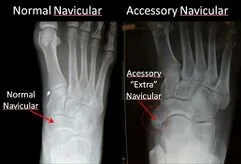

Accessory Navicular

An accessory navicular is an extra piece of bone or cartilage located in the tendon that attaches to the navicular bone on the inner side of your foot, near the arch. It’s not present at birth and can develop over time, often becoming symptomatic during adolescence when bones and cartilage are changing, but it can also cause issues in adulthood.